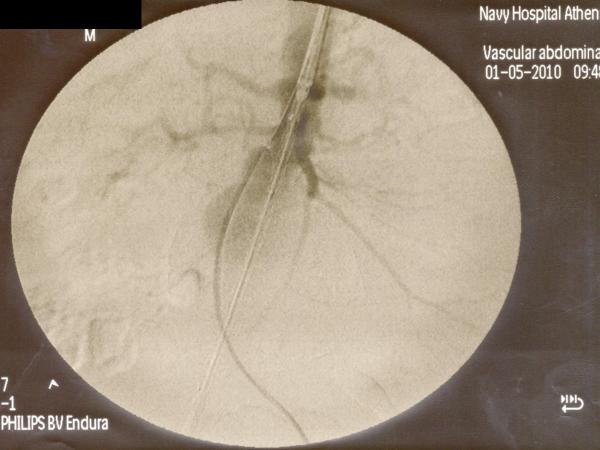

Ενδαγγειακή αποκατάσταση ανευρυσμάτων κοιλιακής αορτής

12ο Πανελλήνιο Συνέδριο Αγγειακής και Ενδαγγειακής Χειρουργικής

2010, Αθήνα